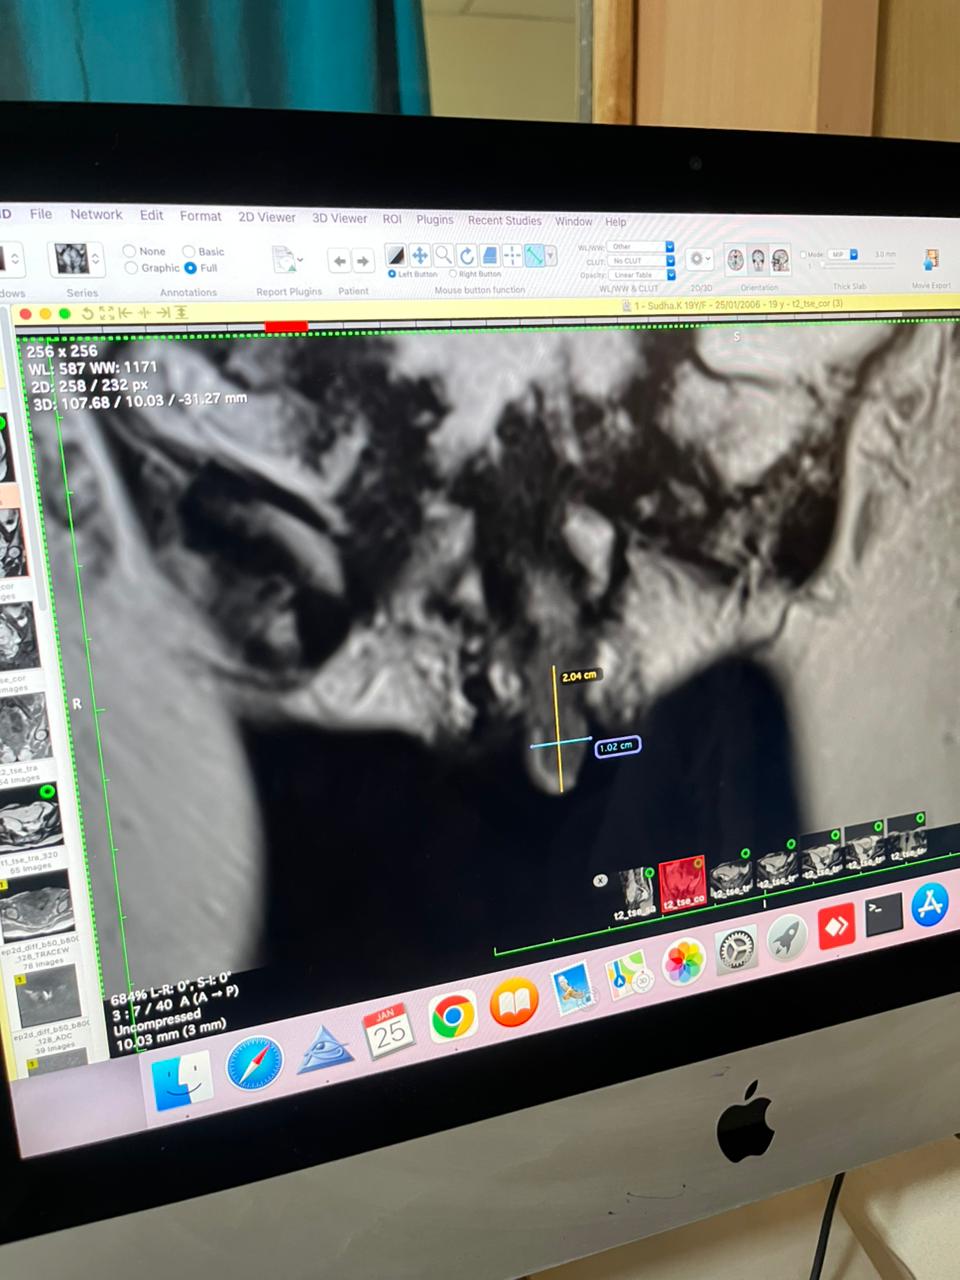

Whatever ambiguity we may have been knowledge biased to have harbored around a possibility of ambiguous genitalia was removed by the subsequent MRI that was again done by our hardworking intern who managed to convince the MS why she needs an academic free MRI πŸ‘πŸ‘

Uterus and ovaries are clearly seen and her bladder that is also seen is partly fashioned from her ileum

PPM 1 - Left ovary πŸ‘†

PPM 1 - Right ovary and adnexal mass. πŸ‘†